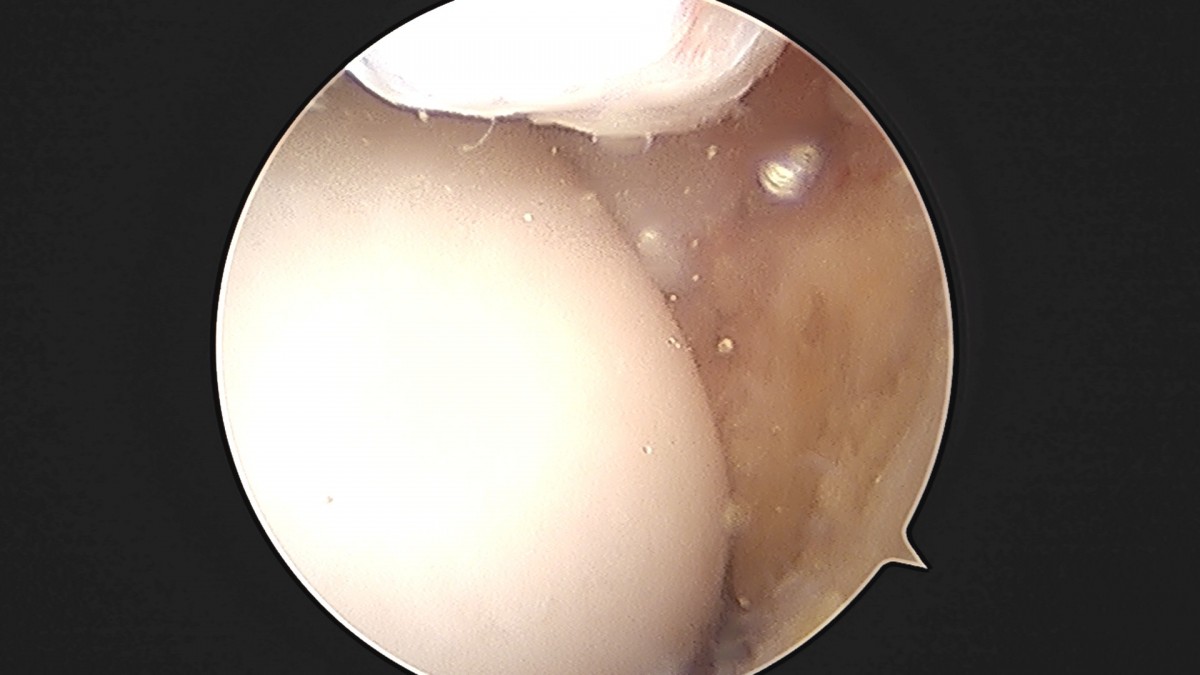

이재상원장님 발목 활액막 절제술 및 인대 봉합술 정보O 환자

dae765e4d9ac96aee867c9d6292d8784_1758003799_5379.jpg